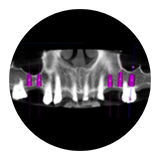

El sistema de implantes dentales SMALL DIAMETER con diferentes diámetros de 1,8 mm, 2,1 mm, 2,4 mm y 2,5 mm. La gran variedad de opciones según el tipo de hueso lo convierten en uno de las mayores gamas de mini implantes dentales en el mercado.